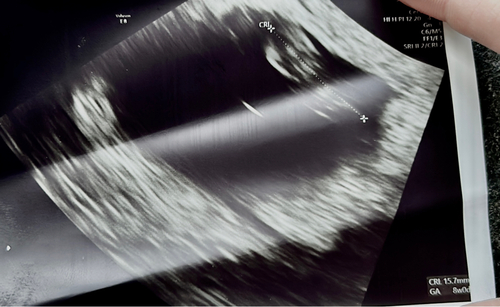

Ik had ook 2 december mijn ovulatie, 12 december licht positief, en op NOD 16 december clear blue digitaal 3+. Ik ben vandaag 8 weken en 3 dagen zwanger, vorige week een echo gehad en die zag er zo uit